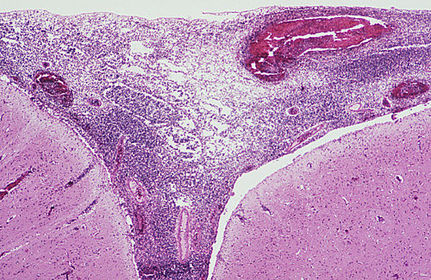

TISSUE TYPE: circular organ .. with lymph follicles .. u see the complete circle... APPENDIX PATHOLOGY: necrotizing tissue in the lumen ... hyperplastic lymph tissue DIAGNOSIS: acute suppurative appendicitis KEY: COMPLETE CIRCLE